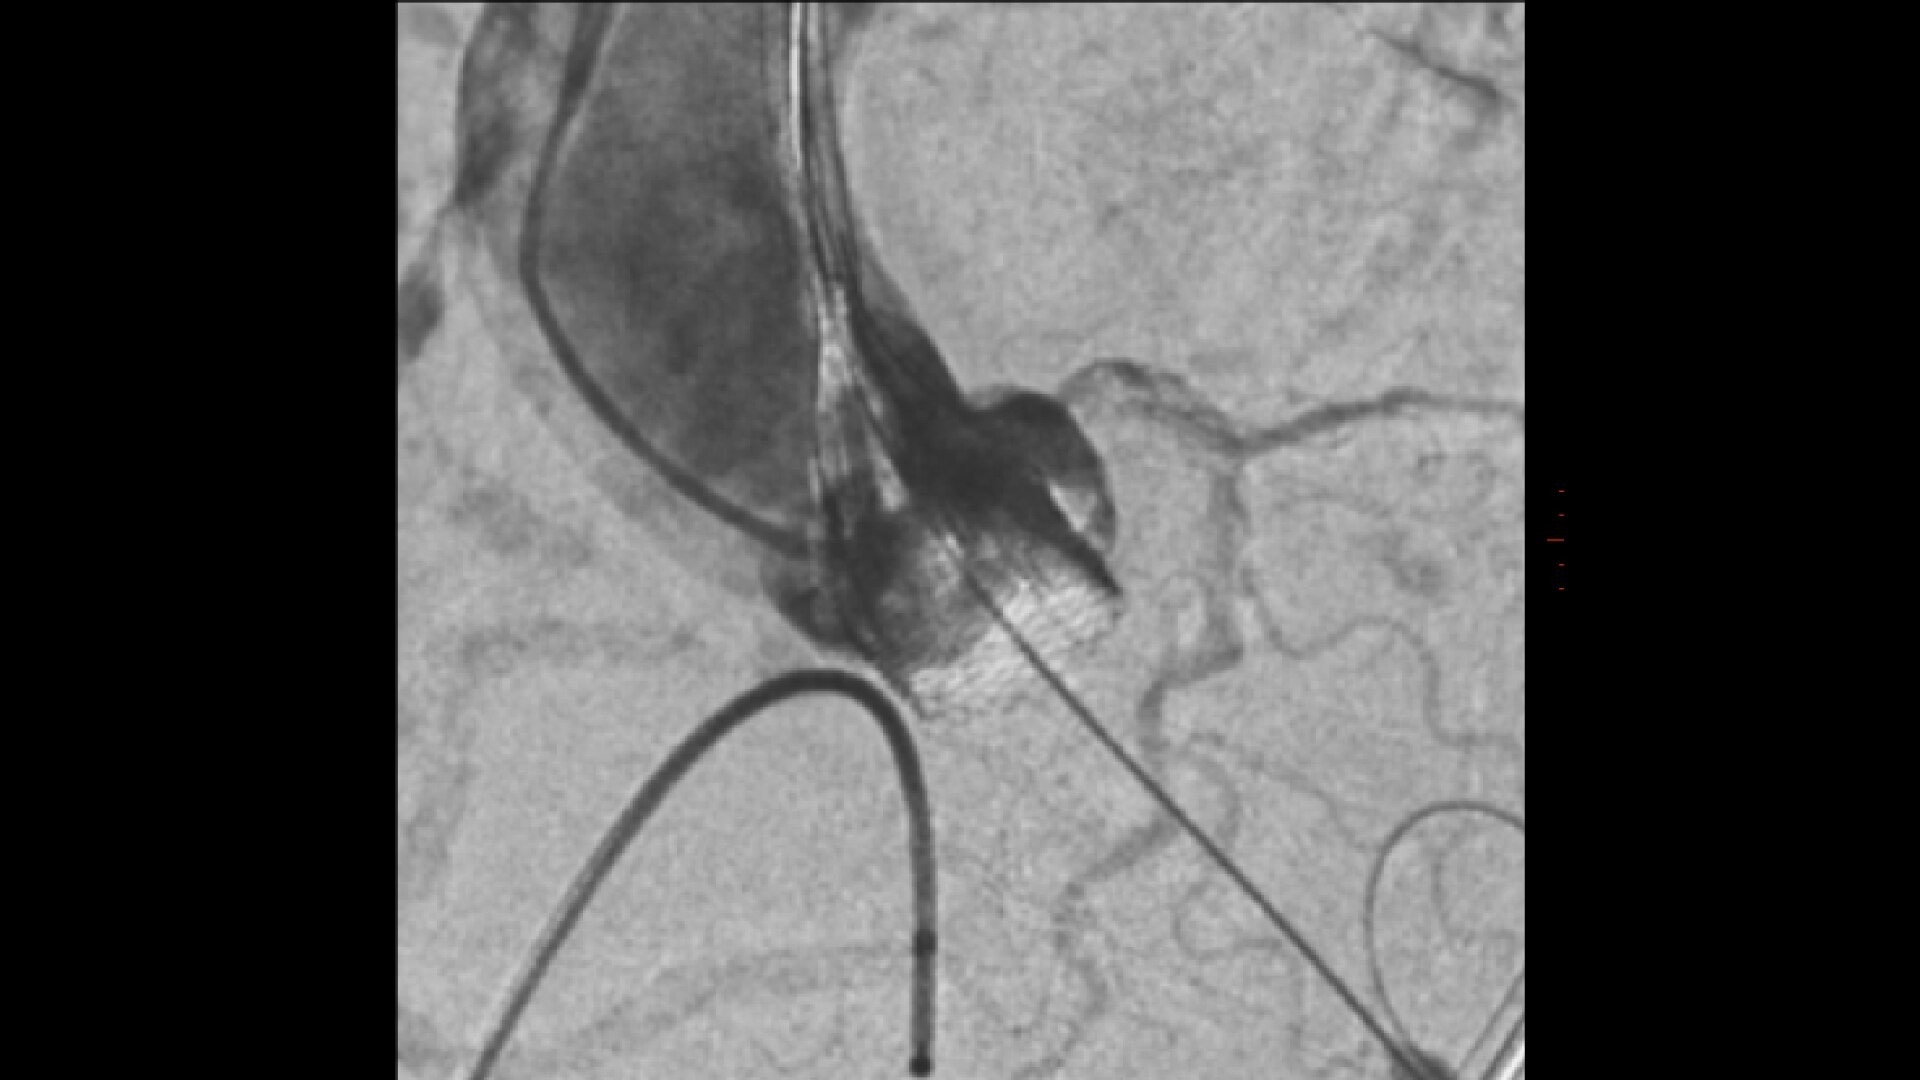

3D fusion guidance enhanced with Calcification Enhancement improves the visualization of moving contrasted structures.